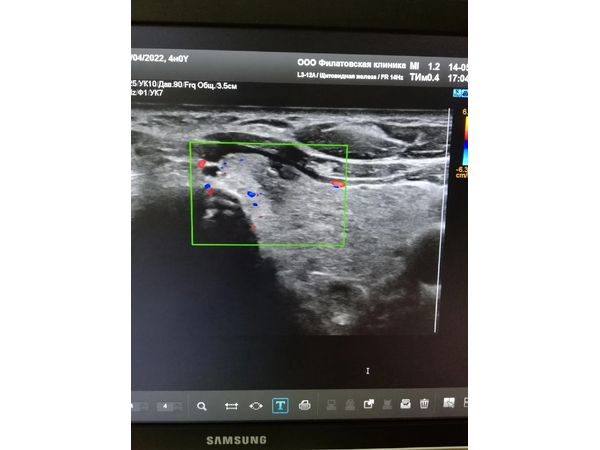

- TI-RADS 4б — округлое изоэхогенное образование размером 1,04×1,23 см с нечёткими, ровными контурами и единичным кальцинатом (0,27×0,23 см), умеренное кровоснабжение по периферии.